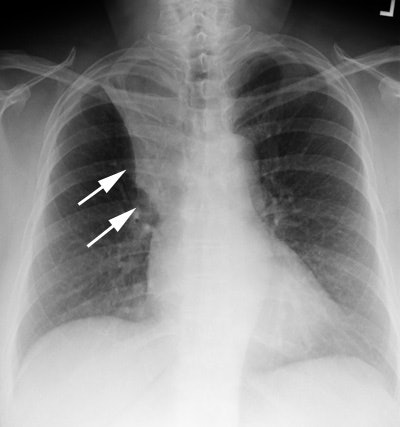

Golden "S" sign:

The patient below presented with a cough. CXR demonstrated a collapsed right upper lobe with a convex bulge along the lower aspect of the collapsed lung (white arrows) producing a "Golden 'S' sign". This finding is concerning for a central mass lesion.  |